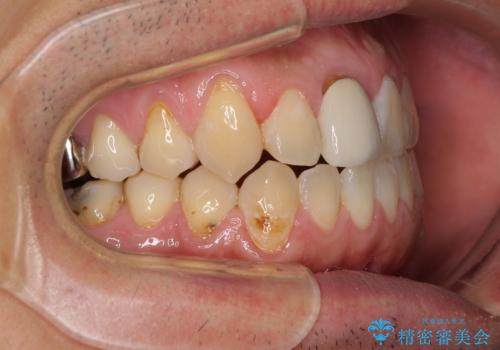

前歯のデコボコとクロスバイトをインビザライン矯正で改善

- 前歯のデコボコと上下のクロスバイトを気にして来院された患者様です。

インビザラインを用い、IPR(歯と歯の間を削る)と歯列全体を拡大させることで、歯並びを整えていくこととしました。

上の前歯が下の前歯を乗り越える際、奥歯がほとんど咬めない時期があり、乗り越えた後も、インビザライン特有の奥歯の咬みにくさが続きました。

咬み合わせ改善のために治療期間を要しましたが、最終的に奥歯はしっかりと咬めるようになりました